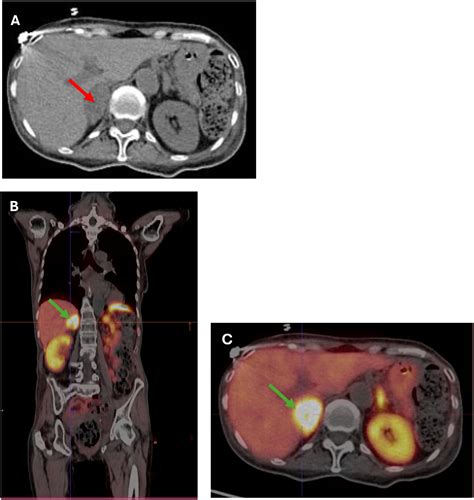

• Imaging studies, such as CT scans or MRIs, to visualize the adrenal glands and pituitary gland